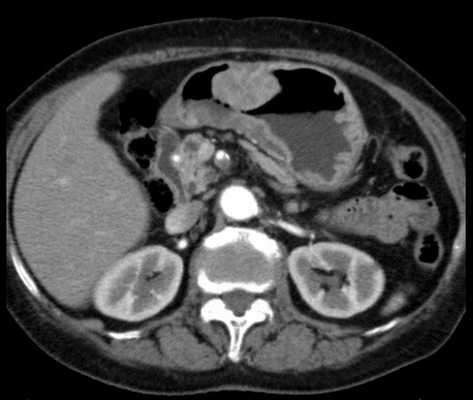

3. КТ при безоаре желудка:

• Четко очерченный внутрипросветный конкремент овоидной формы и низкой плотности:

о Имеет «пятнистый» вид из-за пузырьков газа в структуре

• Большие безоары имеют тенденцию к заполнению просвета желудка

• Маленькие безоары имеют округлую или овоидную форму, имеют тенденцию к расположению на поверхности жидкого содержимого желудка на уровне раздела сред (жидкости и газа):

о Контрастное вещество, принятое перорально, может быть обнаружено вокруг безоара, т. к. свободно располагается в просвете желудка

• Безоар может иметь «слоистый» вид